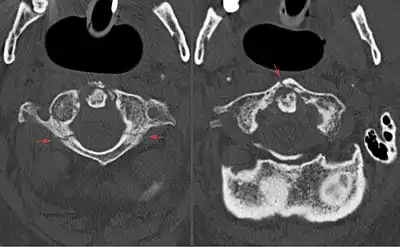

Axial CT scan showing a Jefferson fracture.

Jefferson fracture is often caused by an impact or load on the back of the head, and are frequently associated with diving into shallow water, impact against the roof of a vehicle and falls,[5] and in children may occur due to falls from playground equipment.[6] Less frequently, strong rotation of the head may also result in Jefferson fractures.[5]